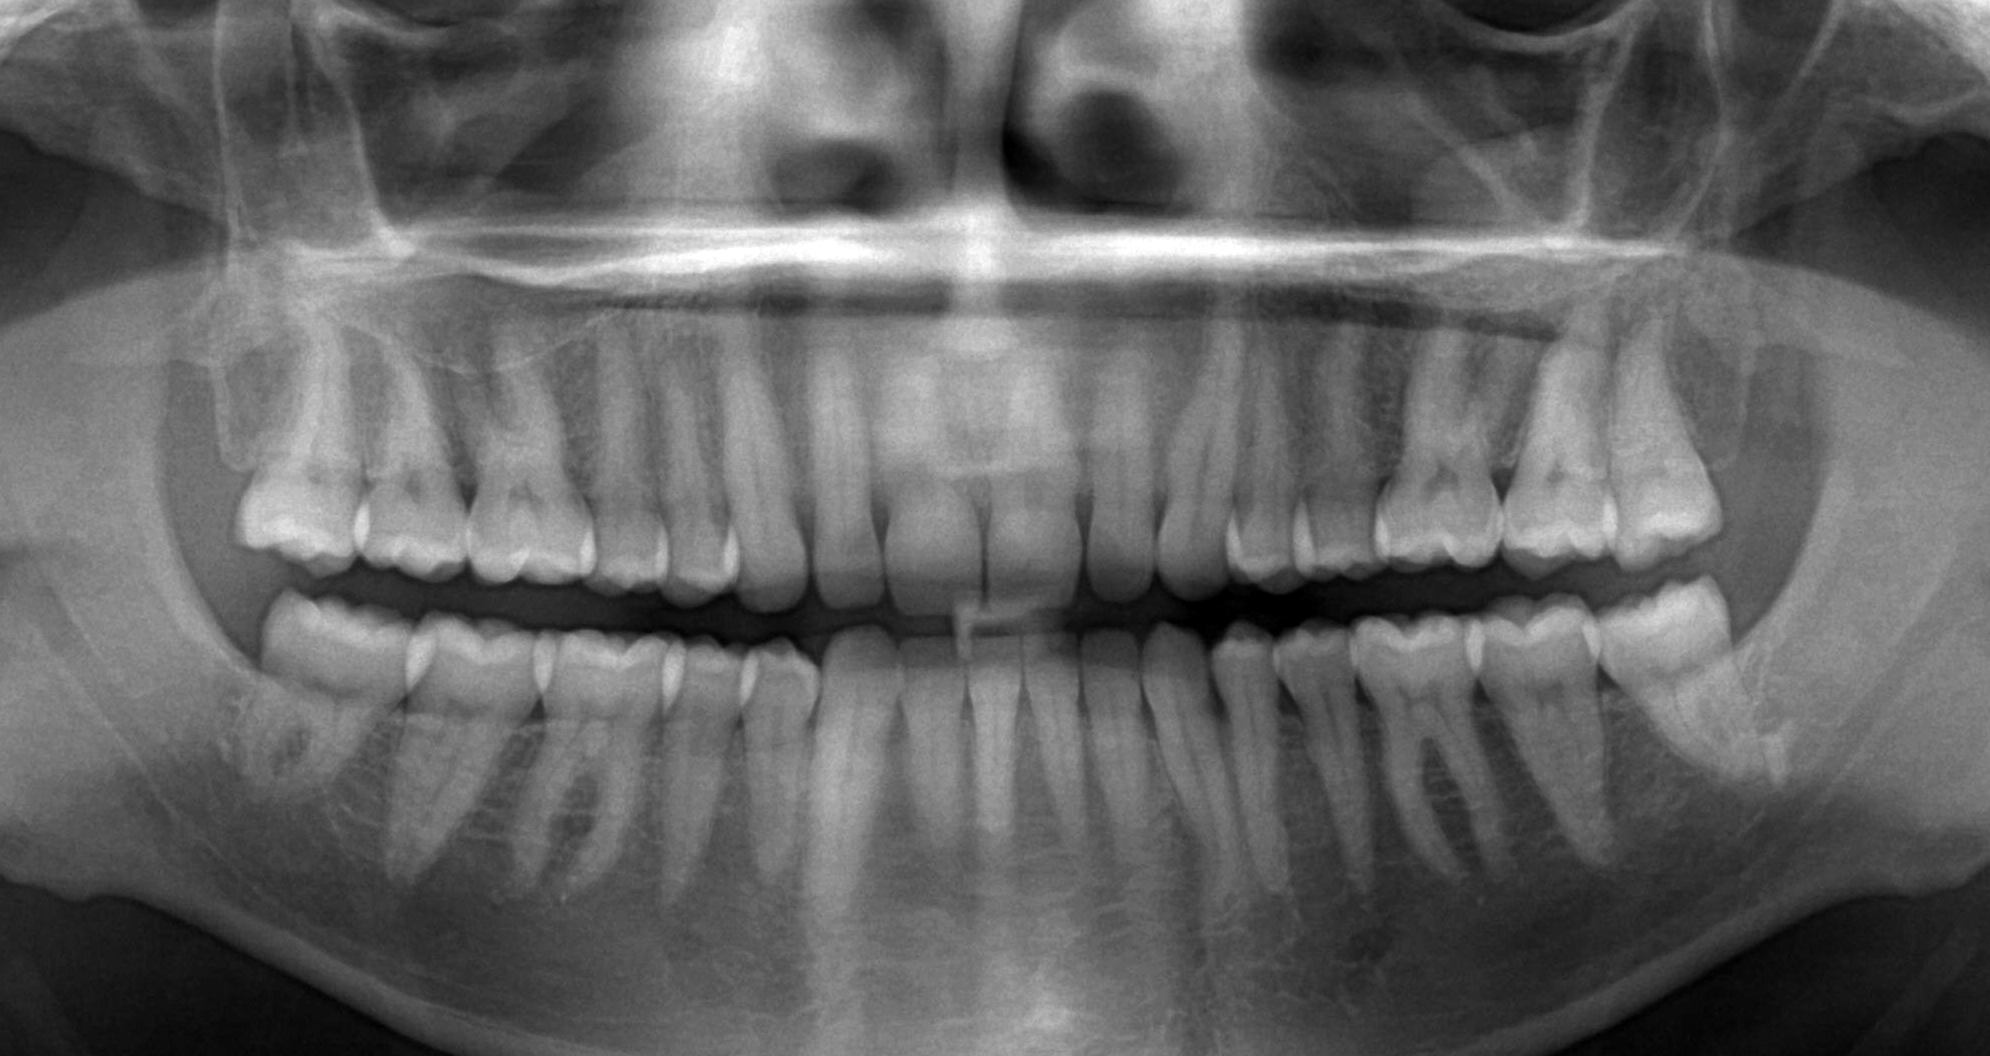

Ортопантомограмма (ОПТГ) — это рентгеновское изображение, на котором одновременно видны обе челюсти, мягкие ткани и костные структуры. Качественный панорамный снимок дает стоматологу полное представление о состоянии зубочелюстного аппарата.

В полости рта можно визуально оценить лишь около 50% тканей. Скрытые проблемы хорошо отображаются на ОПТГ, что делает этот метод необходимым для точной диагностики. Снимок может быть представлен на бумаге, рентгеновской пленке или в цифровом формате для анализа на компьютере.

При интерпретации панорамного снимка можно выявить:

- скрытые кариозные полости на контактных поверхностях зубов;

- кариозные поражения корней;

- наличие кист, гранулем и других изменений в области корней;

- состояние межзубных перегородок и тканей периодонта;

- стадии прорезывания зубов у детей;

- наличие ретенированных зубов;

- новообразования в челюстных костях;

- состояние гайморовых пазух.

Как выглядит ОПТГ?